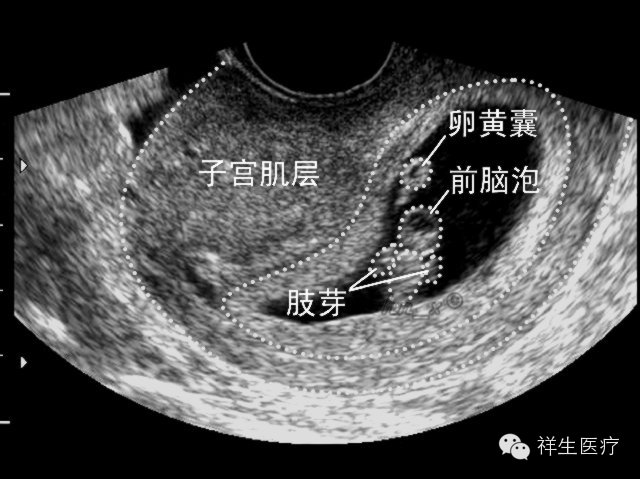

3.孕7周:心脏搏动明显,可显示胎体头极和尾极,并见小肢芽,这时候三维超声会看见宝宝像一个小蚕豆一样。